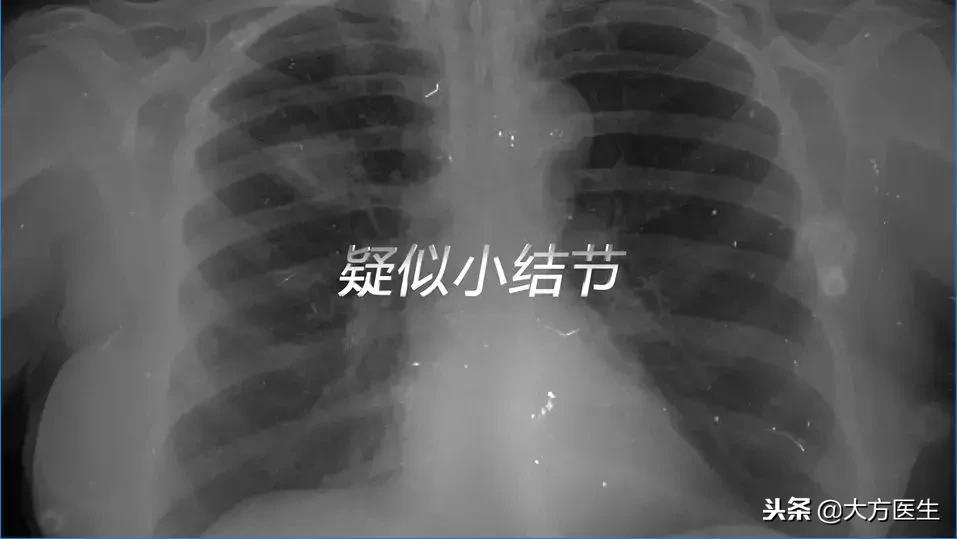

患 者:大夫,我的体检报告说我肺里有个叫什么“疑似”小结节。

不同的检查手段都有其不同的优点和缺点。比如,常规的胸片可以把胸部的整体情况一览无余,然而分辨率就无法让人满意。直径小于1㎝的这种细小结节就不容易在胸片上看清楚,尤其是早期发生的肺癌,胸片几乎对其无能为力。这个时候就需要使用CT检查,对于肺癌的早期筛查尤其重要。只有针对高危人群进行早期肺癌筛查,才能有机会进行手术的根治治疗。